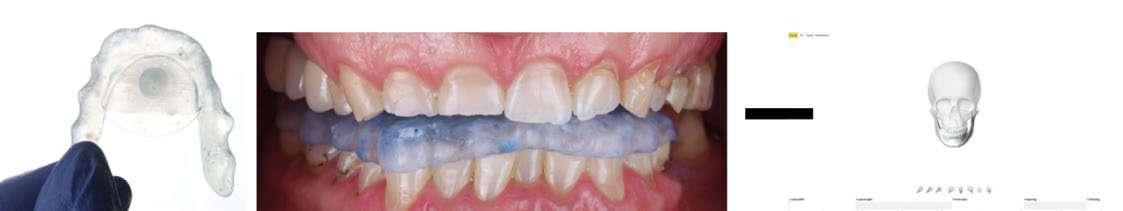

Integración de ortodoncia mediante el sistema Invisalign Go™ para facilitar la restauración en una rehabilitación integral siguiendo los conceptos de mínima invasión en un paciente con desgaste severo.

La adopción de flujos de trabajo digitales ha transformado esta colaboración. El uso de registros tridimensionales, diseños virtuales del plan de tratamiento, y la capacidad de compartir información entre profesionales aseguran una mayor precisión diagnóstica, planificación adaptada al paciente y reducción de la invasividad de los procedimientos, contribuyendo además a una mayor satisfacción de los pacientes.

Dentro de estas tecnologías, el concepto de Prosthetic Guided Orthodontics (PGO) ortodoncia guiada por objetivos protésicos ha emergido como una herramienta eficaz (1,2). En particular, el sistema Invisalign Go™ permite una planificación ortodóncica previa al tratamiento protésico, facilitando la posición e inclinación dental ideales para minimizar la eliminación de tejido dental y optimizar la estabilidad oclusal.

Se recopilaron registros clínicos como fotografías extraorales e intraorales (Fig. 1–6) y digitales completos, incluyendo escaneados intraorales y registros de movimientos mandibulares. Los datos se integraron en un articulador virtual mediante el software de diseño digital (Exocad), montando los modelos maxilares, archivo de movimientos mandibulares y horquilla en formato STL.

Se planificó un aumento de ambas arcadas. La nueva dimensión vertical de oclusión (DVO) se determinó mediante un arco gótico y se validó con registros de movimientos laterales y protrusivos obtenidos con el sistema Zebris (Fig. 7–9). Y se procedió a realizar un CBCT con arco gótico colocado para validar la posición intermaxilar.

1. Ortodoncia Invisalign Go™: corrección de apiñamiento inferior, aumento de resalte y optimización de márgenes gingivales.

2. Rehabilitación protésica: carillas anteriores e incrustaciones de disilicato de litio, junto con puentes posteriores en zirconia monolítica (1.5–1.7 y 3.5–3.7).

3. Provisionalización posterior con técnica de composite estampado y guías de silicona transparente (Fig. 10–21).

sultante del desgaste severo. Una vez establecida la provisionalización de larga duración y determinada la nueva dimensión vertical de oclusión, se tomaron los registros necesarios para iniciar la fase de alineación ortodóncica con el sistema Invisalign Go™. Dichos registros incluyeron escaneados intraorales de ambas arcadas y una secuencia fotográfica completa obtenida mediante la aplicación Invisalign PracticeApp®.

A través de la planificación digital en el ClinCheck® Software, se determinaron los movimientos ortodóncicos indicados, que incluyeron: aumento del resalte, corrección del apiñamiento inferior y una combinación de intrusión y extrusión con el objetivo de nivelar márgenes gingivales. Todos estos mo-

vimientos fueron diseñados considerando la fase restauradora posterior. El resultado de la planificación digital de los movimientos ortodóncicos obtuvimos: 19 alineadores en total, 7 superiores y 19 inferiores, los cuales se indicaron cambios cada 7 días como recomienda la casa comercial y se le explicó al paciente la importancia de utilizar los alineadores entre 20 a 22 horas al día. En dicha planificación también se aplicaron ataches estratégicos y se realizaron desgastes interproximales (IPR 0,2–0,3 mm). Se realizaron controles periódicos cada 4 alineadores, en los cuales observamos mejoras progresivas del apiñamiento inferior y la generación controlada de diastemas superiores tal como los planificamos en el software.